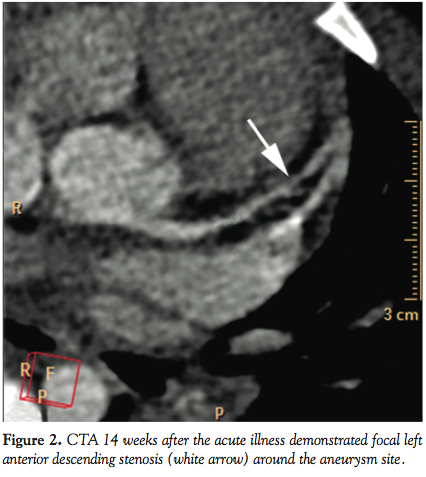

demonstrated structurally normal coronary arteries and heart function. Echocardiogram 6 weeks later suggested a 5 mm fusiform aneurysm in the left anterior descending artery (LAD) and a 4.3 mm saccular aneurysm in the right coronary artery (Figures 1A and 1B). Cardiac computed tomography angiography (CTA) performed at 14 weeks after the acute illness demonstrated focal LAD stenosis at the aneurysmal site described above (Figure 2). Subsequent coronary angiography revealed a severe stenosis in the proximal LAD-diagonal bifurcation (Figure 3). Fractional flow reserve (FFR) evaluation of LAD was performed with escalating doses of intracoronary adenosine: FFR with 12 µg, 24 µg, 36 µg, and 60 µg of adenosine was 0.73, 0.67, 0.64, and 0.63, respectively (Figure 4); FFR of the diagonal branch at maximum hyperemia was 0.61.